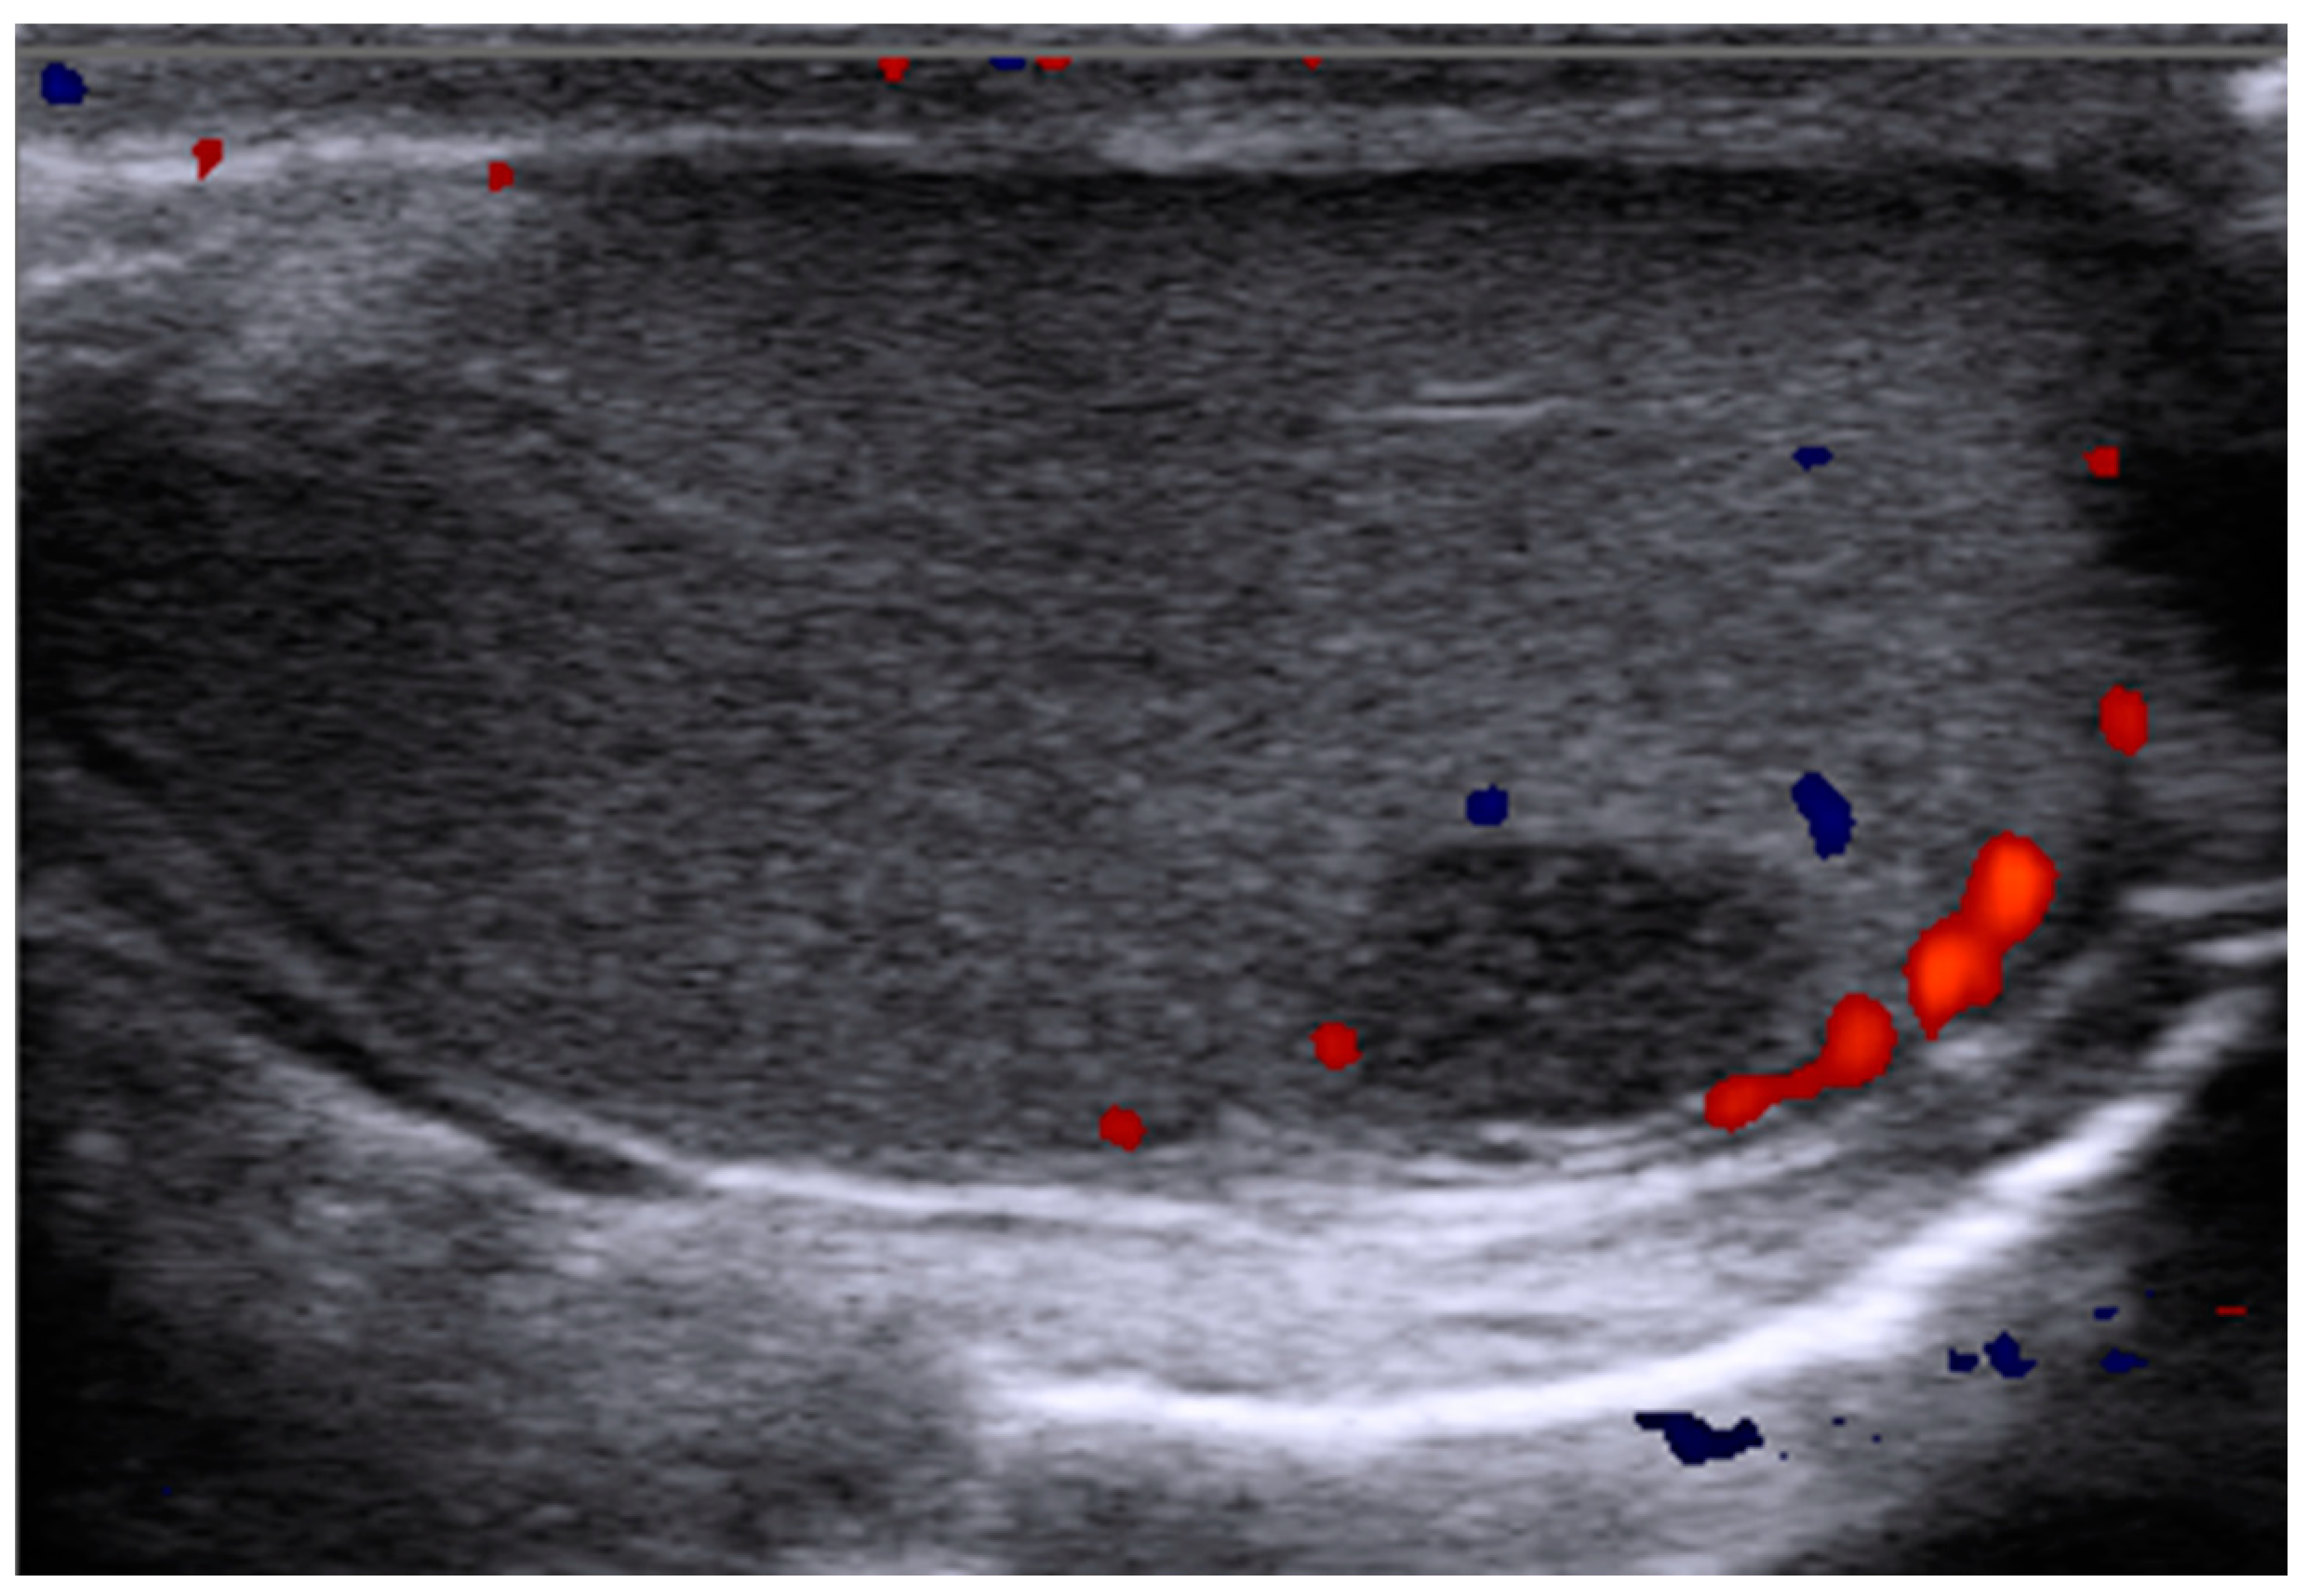

2.2. Non-Specific Small Testicular Masses